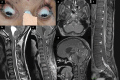

Tuberculosis (TB) is a global health concern and central nervous system (CNS) TB leads to high mortality and morbidity. CNS TB can manifest as tubercular meningitis, tuberculoma, myelitis, and arachnoiditis. Neuro-ophthalmological involvement by TB can lead to permanent blindness, ocular nerve palsies and gaze restriction. Visual impairment is a dreaded complication of tubercular meningitis (TBM), which can result from visual pathway involvement at different levels with varying pathogenesis. Efferent pathway involvement includes cranial nerve palsies and disorders of gaze. The purpose of this review is to outline the various neuro-ophthalmological manifestations of TB along with a description of their unique pathogenesis and management. Optochiasmatic arachnoiditis and tuberculomas are the most common causes of vision loss followed by chronic papilloedema. Abducens nerve palsy is the most commonly seen ocular nerve palsy in TBM. Gaze palsies with deficits in saccades and pursuits can occur due to brainstem tuberculomas. Corticosteroids are the cornerstone in the management of paradoxical reactions, but other immunomodulators such as thalidomide and infliximab are being explored. Toxic optic neuropathy caused by ethambutol necessitates careful monitoring and immediate drug discontinuation. Cerebrospinal fluid diversion through ventriculo-peritoneal shunting may be required in patients with hydrocephalus in stage I and II of TBM to prevent visual impairment. Early diagnosis and prompt management are crucial to prevent permanent disability. Prevention strategies, public health initiatives, regular follow-up and timely intervention are essential in reducing the burden of CNS TB and its neuro-ophthalmological complications.